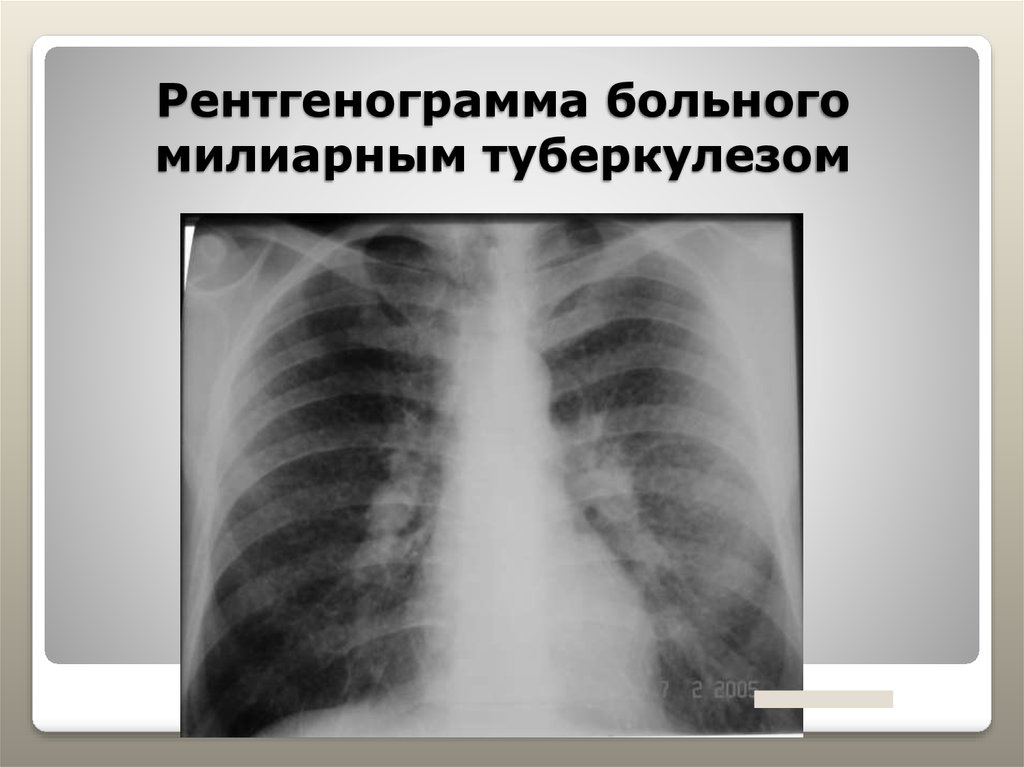

Симптомы и лечение инфильтративного туберкулеза легких

Раздел: Снимки-откровения